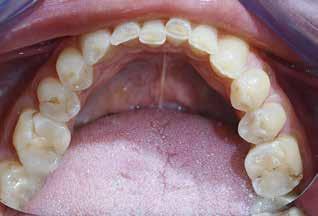

Okklusalt billede af A) over- og B) underkæbe

2. Klinisk ses tydelig slitage ind i dentinen på samtlige tænder fra 6’er til 6’er i begge kæber.

Fig. 2. Clinically, extensive wear into the dentin of all teeth in both jaws is observed.

Klinisk undersøgelse viste et tandsæt med enkelte restaureringer, men med slitagedefekter okklusalt/incisalt på samtlige tænder fra 6’er til 6’er i over- og underkæbe (Fig. 2). Defekterne strakte sig tydeligt ind i dentinen. Baseret på anamnesen og de kliniske fund blev erosion set som hovedårsagen til tandsliddet, mens attrition formodedes at være en medvirkende faktor.